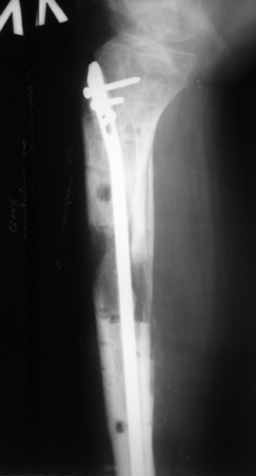

Больному выполнена резекция малоберцовой кости, ВХО раны, сближение отломков. Резекция м\б через отдельный разрез. После ВХО компрессия в аппарате, края раны сближены наводящими швами (без натяжения).

В случае гладкого заживления раны, при условии положительного решения вопроса с металлом, планируем перемонтаж аппарата Илизарова, дополнительную резекцию дистального отломка, выведение полокости голеностопного сустава в правильное положение (см. боковую Р-грамму), одномоментно остеотомия большеберцовой кости. После восстановления длинны голени, по всей видимости, артродез голеностопного сустава.

Рентгенограммы прилагаются. Фото местного статуса выложу в ближайшее время.

Мы обычно не фиксируем малоберцовую кость. Просто стараемся сопоставить ее концы за счет хорошей репозиции. В представленном случае имеется некоторое смещение дистальных фрагментов кнаружи, и, как мне кажется, ротация их вместе со стопой кнутри (ротация хорошо заметна на прямом снимке по форме таранной кости и на боковом по соотношению отломков малоберцовой). Если это действительно так, то это несложно сейчас постепенно устранить в аппарате. И тогда концы малоберцовой кости будут находиться поближе друг к другу.